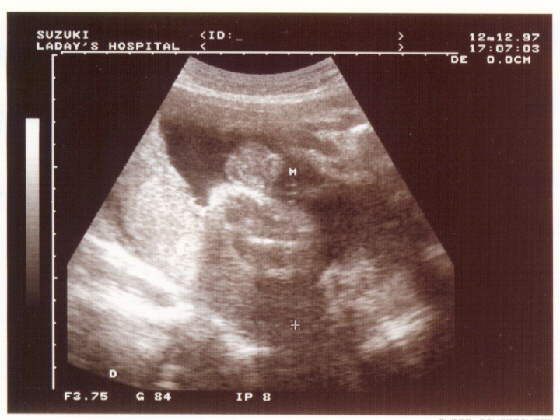

わたしの息子

性別判明

平成9年12月12日

私たちはあなたの誕生を心待ちにしています